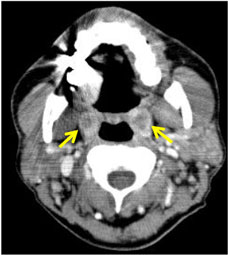

(3) 이미징 검사 : 결석이 크거나 복잡한 경우, CT나 X-ray 촬영을 통해 크기와 위치를 분석합니다.